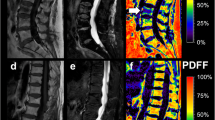

Several studies applied quantitative DWI to normal and pathological vertebral bone marrow. Although the results showed a certain variability, the majority of the studies revealed typical ADC ranges associated with normal and pathological bone marrow. Normal bone marrow shows ADCs of 0.2–0.5 × 10−3 mm2/s. Metastases or malignant fractures range from ~0.7 to 1.0 × 10−3 mm2/s, osteoporotic or traumatic fractures show ADCs of ~1.0–2.0 × 10−3 mm2/s (Dietrich et al. 2009). Studies always showed a remarkable overlap, which limited the value of quantitative DWI in differentiating between benign and malignant fractures. Figures 12 and 13 show the ADC maps of a malignant and an osteoporotic fracture.

3.2 In-Phase/Opposed-Phase (Chemical-Shift) Imaging

In-phase (IP)/opposed-phase (OP) imaging (also known as chemical-shift imaging) uses the different precession frequencies of water and fat protons due to the differences in their molecular environment. Water and fat protons are in-phase with one another at a TE of 4.6 ms, and 180° opposed at a TE of 2.3 ms at 1.5 T. When there are both fat and water protons in a given voxel, there will be some signal intensity loss on images that are obtained, when the protons are in their opposed-phase, without a refocusing pulse. More signal intensity loss occurs when the volume of fat and water is roughly equal (Erly et al. 2006). The percentage decrease of the bone marrow signal intensity on opposed-phase images compared with in-phase images (Zajick et al. 2005) or the relative signal intensity ratio (signal intensityOP/signal intensityIP) (Eito et al. 2004; Erly et al. 2006) can be calculated for quantitative measurement.

Normal vertebral bone marrow has fat and water components. In adults, the vertebrae, sternum, and ribs contain hematopoietic red marrow, which has about 40% fat content while yellow marrow contains 80% fat (Eastell 2007). Malignant neoplasms tend to replace the fatty marrow components and therefore cause a lack of suppression on the opposed-phase images. Benign vertebral fractures usually show no marrow displacement, which results in low signal intensity on the opposed-phase images (Baker et al. 1990; Eito et al. 2004; Zajick et al. 2005; Erly et al. 2006). Figures 14 and 15 show the IP and OP images and the calculated ratios of an osteoporotic and a malignant vertebral fracture.